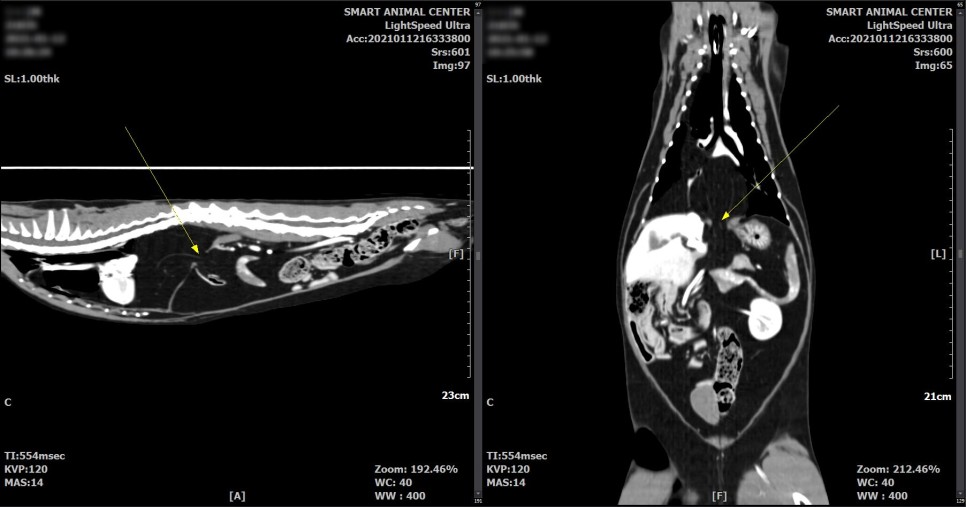

보다 면밀한 흉부 평가를 위해서 CT촬영을 실시했습니다.

CT 검사 결과

횡격막의 일부 결손 부위와 흉강 내 다량의 지방 병변이 확인되었습니다.

횡격막 결손부에 의한 다량의 지방 디스크가 있을 수 있으며,

또한 영상학적으로 악성도를 지시하는 것과 같은 소견은 관찰되지 않았습니다.

다량의 지방으로 폐 실질 등, 왼쪽 변위가 유발되고 있다고 판단되었습니다.